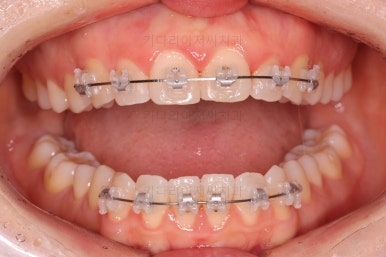

부산나비앞니교정 키다리아저씨치과에서 치료를 한 지 3개월째의 모습입니다.

굉장히 많이 가지런해 진 것을 볼 수 있어요.

그래도 여전히 나비앞니의 느낌이 남아있어서 미세한 조절을 더 하고 마무리를 하기로 했습니다.